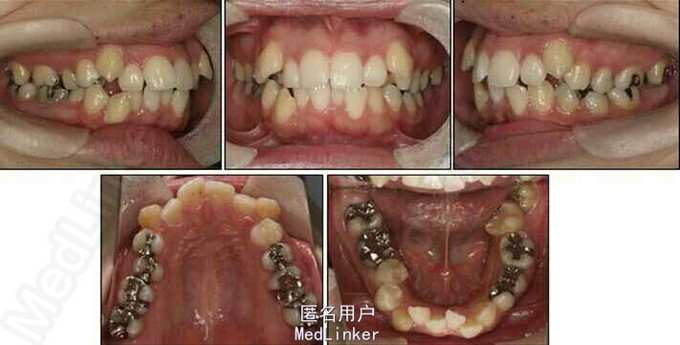

24岁女性,主诉前牙拥挤,左侧第二磨牙严重向舌侧倾斜,左侧咀嚼困难因为第二磨牙锁合,要求解决。

面部:凸面型,上下唇前突,上唇E线前3.5mm,下唇E线前9.5mm,闭唇时口周肌肉紧张。口内检查:双侧尖牙磨牙I类关系,左侧7锁合,覆盖4.5mm,覆合1mm,中线正,上颌拥挤度12.5mm,下颌拥挤度8.2mm。全景片示4个第三磨牙均阻生,怀疑上颌第二磨牙远中面因8阻生有牙根吸收,下颌8近中倾斜阻生更严重,右下6、左下4和5都行了RCT并大面积充填。头影测量示骨性I类,高角,下切牙唇倾。无TMJ症状,只是咀嚼测试时,右侧(非锁合侧)较左侧速度更快且更稳定。

诊断:安氏II类1分类,双颌前突,牙列严重拥挤,左下7锁合,双侧上7牙根吸收,四颗第三磨牙阻生 治疗目标:减少唇的突度及前牙拥挤,扶正4颗阻生的第三磨牙,达到良好的面部美观和功能咬合。 治疗:上颌拔除2颗5和2颗7(不拔4的原因为左上4为正常牙,左上5大面积充填;右上4形态较右上5好。因拔除了坏牙保留了健康牙齿,但是拔5不利于前牙的内收,所以于上后牙56之间植入了支抗钉加强支抗,辅助内收前牙。拔7原因为两颗7远中面均有牙根吸收且有大面积充填),下颌左侧拔除5和7(左下5根管治疗且根尖阴影,拔除左下7原因为严重锁合,改正困难且容易导致上下磨牙的伸长加重II类高角面型),右侧拔除根管治疗且大面积充填后的6;分别竖直4颗近中倾斜阻生的8,整个疗程39个月,四颗8成功的代替6或7。双侧I类尖牙关系,左侧磨牙I类关系,右侧磨牙完全远中关系。唇突度改善,全景片可见达到可接受的牙根平行度,4个8完全萌出直立。以前因为锁合导致的两侧咬合不对称没有了。